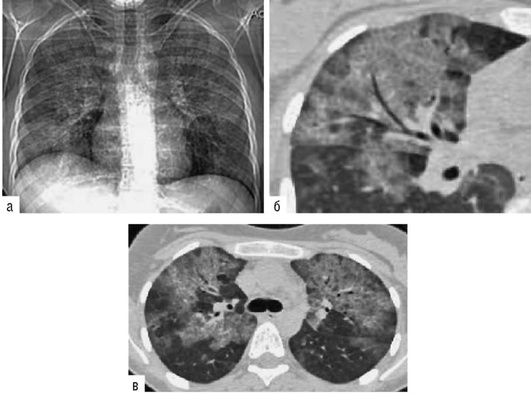

Лучевые методы исследования. Рентгенологическая картина при ЭТА зависит от стадии заболевания. В начальной фазе выявляются признаки отека интерстициальной ткани легких и распространенные мелкоочаговые затенения. При прогрессировании процесса формируются двусторонние изменения легочного рисунка по типу интерстициального фиброза, преимущественно в нижних отделах легких (рис. 2.28). В далеко зашедших случаях определяется мелко- и крупноячеистая деформация легочного рисунка. Описаны случаи, когда единственным рентгенологическим признаком болезни был односторонний плевральный выпот. Отсутствие каких-либо изменений на рентгенограммах отнюдь не исключает ЭТА. Так, при бериллиозе у 23-59% больных может выявляться умеренно выраженная двусторонняя лимфоаденопатия, а в ряде случаев - рентгенотрицательная форма бериллиоза (Dweik R.A., 2015). У 30% из 71 больных ЭТА, наблюдавшихся нами в клинике пульмонологии, в момент обследования изменений на рентгенограммах не было (Орлова Г.П., 2019). Группа больных ЭТА была обозначена условно как рентгенотрицательная группа. Уточнить диагноз помогает КТ легких, выявляющая интерстициальные изменения в легочной ткани по типу «матового стекла», усиление и деформацию легочного и сосудистого рисунка (рис. 2.29), фиброзные изменения тяжистого и звездчатого типов, на поздних стадиях - «сотовое легкое». ВРКТ выявляет «матовое стекло» и другие изменения в легочной паренхиме, которые не видны при обычном рентгенологическом исследовании. Но даже ВРКТ не всегда выявляет изменения в легочной ткани. Так, в 25% случаев гистологически подтвержденного хронического берил-лиоза легких ВРКТ была нормальной (Dweik R.A., 2013; Амосов В.И., Сперанская А.А., 2015; Amanullah S. et al., 2015).

Рентгенологические изменения в легких при ингаляционных лихорадках также могут отсутствовать или проявляться в виде летучих инфильтратов (Ahsan S.A. et al., 2009; Shimizu T. et al., 2012; Greenberg M.I. et al., 2015). При бериллиозе, помимо диффузных инфильтратов и усиления легочного рисунка, за счет интерстициального компонента у 23-59% больных может выявляться лимфаденопатия (Sirajuddin A. et al., 2009).

Проведенное нами динамическое исследование КТ-паттернов у 42 больных ЭТА показало трансформацию отдельных типов интерстициальных пневмоний по мере прогрессирования патологического процесса в фиброзную НСИП или ОИП (рис. 2.30), что подтверждает объединительную концепцию интерстициальных пневмоний вне зависимости от этиологического фактора, которые являются не отдельными нозологическими формами, а стадиями течения фиброзирующего процесса в легких (Илькович М.М., Новикова Л.Н., 2018; Орлова Г.П. и др., 2019).